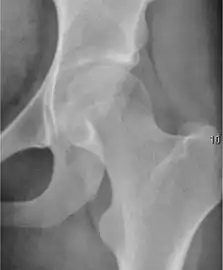

Plain radiography allows us to categorize the hip as normal or dysplastic or with impingement signs (pincer, cam, or a combination of both). Besides these, pathologic processes like osteoarthritis, inflammatory diseases, infection, or tumors can also be identified (Figure 1).[1]

Figure 1.

Radiography in normal hip

X-ray in pincer impingement type of hip dysplasia

X-ray of cam

Hip in osteoarthritis

Septic arthritis

In adults, one of the main indications for radiographs is the detection of osteoarthritic changes (Figure 1(e)). Nevertheless, radiographs usually detect advanced osteoarthritis that can be graded according to the Tönnis classifications. The grading system ranges from 0 to 3, where 0 shows no sign of osteoarthritis. Intermediate grade 1 shows mild sclerosis of the head and acetabulum, slight joint space narrowing, and marginal osteophyte lipping. Grade 2 presents with small cysts in the femoral head or acetabulum, moderate joint space narrowing, and moderate loss of sphericity of the femoral head. Grade 3 is the severest form of osteoarthritis, which manifests as severe narrowing of the joint space, large subchondral cyst with productive bone changes that may lead to deformity of the bone components of the joint, while secondary osteoarthritis due to calcium pyrophosphate deposition can be diagnosed when calcification of hyaline cartilage and fibrocartilage is detected.[1]

There are other pathological conditions that can affect the hip joint and radiographs help to make the appropriate diagnosis. Acute bacterial septic arthritis can be diagnosed by radiographs when a fast regional osteoporosis and destructive monoarticular process develops (Figure 1(f)). In case of tuberculous or brucella arthritis it is manifested as a slow progressive process, and diagnosis may be delayed.[1]